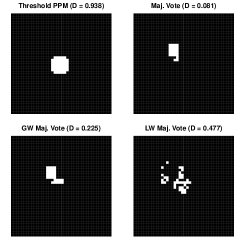

Most existing label fusion procedures result in a binary map corresponding to inclusion/exclusion of voxels in a structure of interest. Thresholding the posterior probability maps at 0.5 also yields such a binary map, displayed in Figure 6. For comparison, the figure also displays the segmentations that result from simple majority voting, globally-weighted majority voting (Artaechevarria et al., 2008) in which each atlas is weighted by the inverse of its average squared intensity difference, and locally-weighted majority voting (Artaechevarria et al., 2009) in which the contribution of each atlas at each pixel is weighted by the inverse squared intensity difference from the target. We can see the superior recovery of the target under our approach versus different versions of majority voting. The figure also gives the Dice similarity coefficients quantifying similarity between each segmentation and the target, where the target is dichotomized to zero / non-zero pixels. Let denote the indicator of inclusion of pixel in the estimated image. The Dice coefficient, calculated as , is often used as a measure of image similarity (though it may not be the best measure when the structure of interest is small relative to the image size (Taha and Hanbury, 2015)). Dice values close to one indicate strong agreement between two images. Despite the fact that all of the poor segmentations were downweighted relative to the good one, they still outweigh the quality atlas in each voting procedure, resulting in poor segmentation. Thresholding the posterior probability map has resulted in improvement in similarity over even the most favorable version of majority voting.

Often, a researcher is uninterested in a binary segmentation for its own sake, but rather as a means to an end; e.g., volume estimation. With a binary segmentation, the only way to estimate the volume is by summing the binary indicators over the image. In contrast, our approach facilitates construction of a distribution of plausible volumes. Let denote the realization of on iteration of the MCMC output. Recognizing that , we estimate the structure volume on iteration with . The right panel in Figure 6 displays the estimated marginal distribution of volume, along with the true volume and the volume estimates obtained from the three voting procedures. The true volume is well within the high probability region of the distribution. We have no way of formally quantifying the uncertainty associated with the voting estimates.